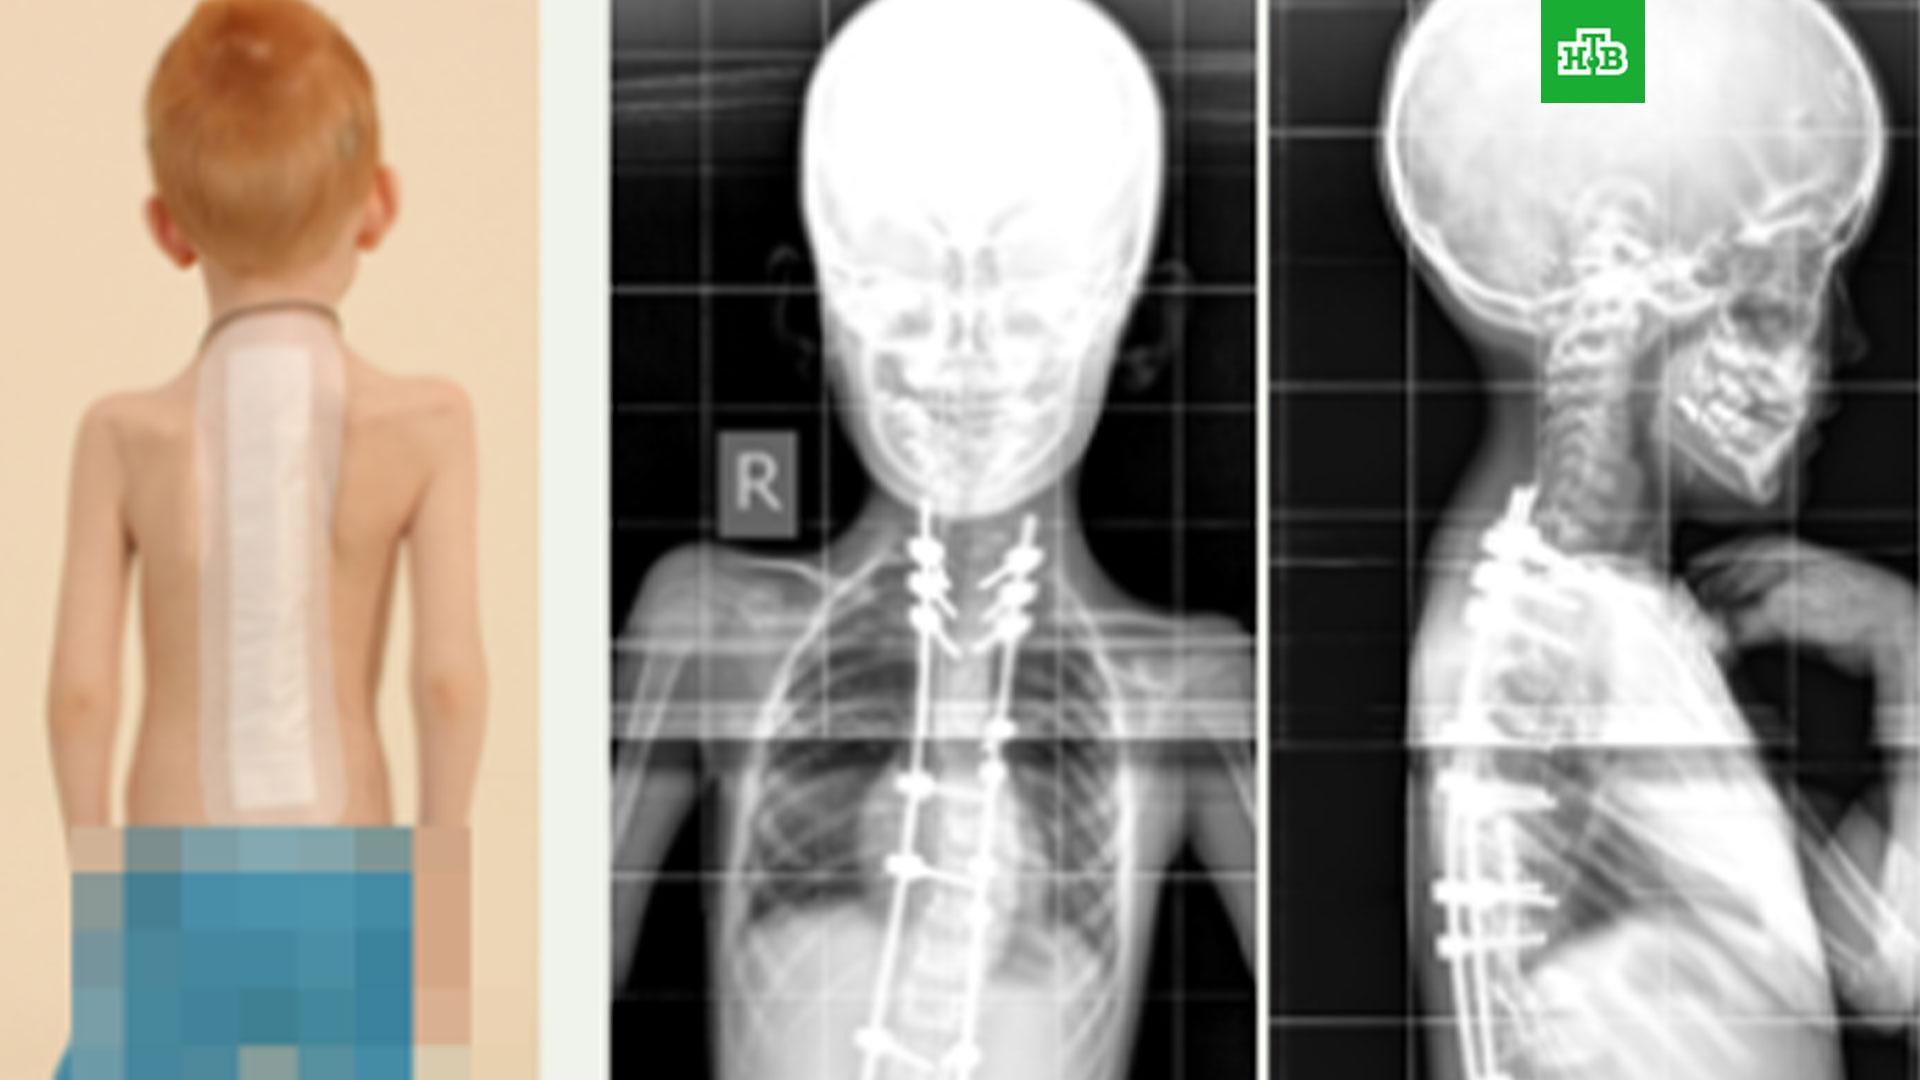

Шесть лет назад ребенок перенес двухэтапную операцию, после чего деформацию позвоночника удалось скорректировать. Сначала врачи сделали

Полина Очирова, вертебролог, кандидат медицинских наук: «Мы выполнили сложное оперативное вмешательство и исправили аномальное положение шейных позвонков, устранили базиллярную импрессию, стеноз позвоночного канала на уровне краниовертебрального перехода, установили погружную металлоконструкцию, для более прочной фиксации и формирования костного блока мы использовали костный трансплантат».